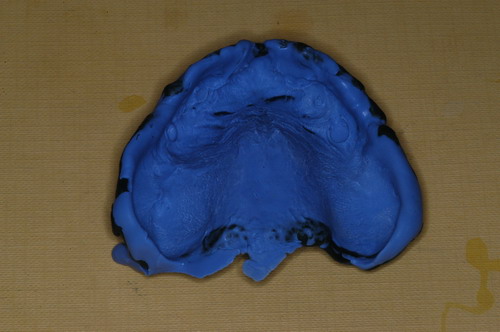

EL USO DEL ARCO GÓTICO DE GYSI , MEDIANTE UNA BÓVEDA PALATINA Y UN APOYO CENTRAL ÚNICO (BO PA YA CU) , EN LA UBICACIÓN DE LA RELACIÓN CÉNTRICA EN UN CASO DE GRAN LAXITUD TENDINOSA CAPSULAR. EL PACIENTE SE PRESENTA A CONSULTA CON UNA EDENTACIÓN PARCIAL, Y GRADO DE MOVILIDAD EXTREMO EN TODAS SUS PIEZAS REMANENTES. SE ESTUDIA EL CASO RADIOGRÁFICA Y CLÍNICAMENTE , Y EL PACIENTE RELATA ESTAR EN ESE ESTADO DESDE HACE MUCHO AÑOS. AL MANIPULAR LA MANDÍBULA EN UN INTENTO DE CONOCER EL ESTADO MUSCULAR DEL SISTEMA, SE OBSERVA UNA GRAN LABILIDAD TENDINOSA CAPSULAR QUE SE MANIFIESTA EN UNA HIPER LAXITUD EN LOS MOVIMIENTOS MANUALMENTE INDUCIDOS DE AMBOS CÓNDILOS DENTRO DE LA CAVIDAD. SE TOMAN IMPRESIONES Y SE MONTA EN UN ARTICULADOR SEMI AJUSTABLE , CORTANDO EN EL YESO LAS PIEZAS QUE SERÁN EXTIRPADAS , CONSERVANDO UNICAMENTE , AMBOS PRIMEROS PREMOLARES INFERIORES , QUE SERÁN UTILIZADOS PARA RETENER MEDIANTE RETENEDORES ELÁSTICOS LA PRÓTESIS INFERIOR , EN LA PRESUNCIÓN DE LA HIPERMOVILIDAD A QUE SERÁ SOMETIDA DADO QUE EN LA GRAN REABSORCIÓN ÓSEA , ES FRECUENTE EL ACERCAMIENTO DE TODAS LAS INSERCIONES MUSCULARES A LA PORCIÓN SUPERIOR DEL REBORDE ÓSEO , LO QUE ATENTARÁ CONTRA LA ESTABILIDAD DE DICHA PRÓTESIS PROVISIONAL. EN UNA PRIMERA SESIÓN CLÍNICO QUIRÚRGICA , SE EXODONCIA TODO EL SECTOR INCISIVO Y CANINO INFERIOR , Y AL OBSERVAR EL REMANENTE ÓSEO CANINO DE AMBOS LADOS , SE IMPLANTA EN FORMA INMEDIATA . TANSCURRIDOS DOS MESES , DONDE LA CICATRIZACIÓN ES ADECUADA , Y LA DINÁMICA MANDIBULAR ACEPTABLE , SE PROCEDE A LA ETAPA QUIRÚRGICA IMPLANTARIA MEDIANTE IMPLANTES SEMI SUMERGIDOS, CON ALGUNAS ZONAS DE REGENERCIÓN ÓSEA GUIADA FIG17 FIG18 FIG19 FIG26 DURANTE LA ETAPA DE CICATRIZACIÓN DE ESTE NUEVO ABORDAJE QUIRÚRGICO , SE ENDODONCIAN AMBOS PREMOLARES INFERIORES CONSERVADOS , LOS QUE EN UN FUTURO , CUANDO YA NO SIRVAN PARA RETENER LA PRÓTESIS REMOVIBLE PROVISORIA INFERIOR , SERÁN CORTADOS COMO RESERVA DE CAPITAL ÓSEO O BIEN COMO ELEMENTO RETENEDOR ANTE CUALQUIER TIPO DE INCIDENCIA IMPLANTARIA. ABORDAMOS LA ETAPA PRIMARIA PROTÉTICA , UNA VEZ TRANSCURRIDOS TRES MESES, MEDIANTE LA UTILIZACIÓN DE CUBETAS INDIVIDUALES , A LAS QUE REALIZAMOS UN RECORTE MUSCULAR EN BASE A STENS VERDE , COMO SI DE UNA PRÓTESIS COMPLETA SE TRATARA. DE ESE MONTAJE OBTENEMOS DOS RODETES DE METACRILATO , PERFECTAMENTE ADAPTADOS A LOS MODELOS FUNCIONALES , A LOS QUE LES OTORGAMOS LA PLANIMETRÍA DERIVADA DEL PARALELISMO CON EL PLANO DE FRANKFURT , Y UNA ALTURA (DV) QUE RESULTA DE LOS MÉTODOS MÉTRICOS DE DIMENSIÓN VERTICAL… Y QUE NOS SERVIRAN ADEMÁS DE TOMAR UNA NUEVA IMPRESIÓN FUNCIONAL MEDIANTE RECORTE MUSCULAR , PARA ADAPTAR UN DISPOSITIVO CONSISENTE EN UNA BÓVEDA PALATINA SUPERIOR , Y UN TORNILLO CENTRAL INFERIOR , LOS QUE DESPUÉS DE UN ENTRENAMIENTO ADECUADO DEL ENFERMO , NOS PERMITIRÁ REPRODUCIR EN EL BÓVEDA , EL ARCO GÓTICO DE GYSI , ENCONTRANDO DE ESTA MANERA LA OCLUSIÓN EN RELACIÓN CÉNTRICA. ACTUALMENTE ESTE MÉTODO HA SIDO RECREADO MEDIANTE LA DENOMINACIÓN DE: FIG50 FIG51 FIG52 OBTENIDO EL DIBUJO DEL ARCO GÓTICO , INSINUAMOS EN EL VÉRTICE DEL MISMO UNA PERFORACIÓN QUE FIJARÁ LA PUNTA DEL TORNILLO EN ESA POSICIÓN: RELACIÓN CÉNTICA FIG55 FIG56 FIG57 CON ESTOS PARÁMETROS SE CONSTRUYEN DOS SOBREDENTADURAS ABROCHADAS EN RÓTULAS SUPRA IMPLANTES , QUE LE OTORGAN FIJACIÓN SUFICIENTE , DANDO A LA OCLUSIÓN TODOS LOS ELEMENTOS DE UNA: OCLUSIÓN MUTUAMENTE COMPARTIDA, REFERENCIA II CON UN ESQUEMA OCLUSAL DE : FUNCIÓN DE GRUPO BILATERAL POSTERIOR DE ACCIÓN CANINA DESPUÉS DE LAS REVISIONES PERTINENTES A LA SEMANA , EL MES Y LOS SEIS MESES DE TERMINADA LA REHABILITACIÓN , SE CITA AL ENFERMO PARA UN NUEVO CONTROL AL AÑO Y MEDIO Y SE OBSERVA UNA PERFECTA SITUACIÓN TISULAR , CLINICA Y RADIOGRAFICAMENTE CONTROLADA , Y ADEMÁS LA PERMANENCIA DEL MISMO ESQUEMA OCLUSAL OTORGADO DESDE EL PRINCIPIO. SE CONTROLA RADIOGRAFICAMENTE Y SE DA EL ALTA DEFINITIVA RECOMENDANDO EL CONTROL DOS VECES AL AÑO. REFERENCIAS: I : II. : III: